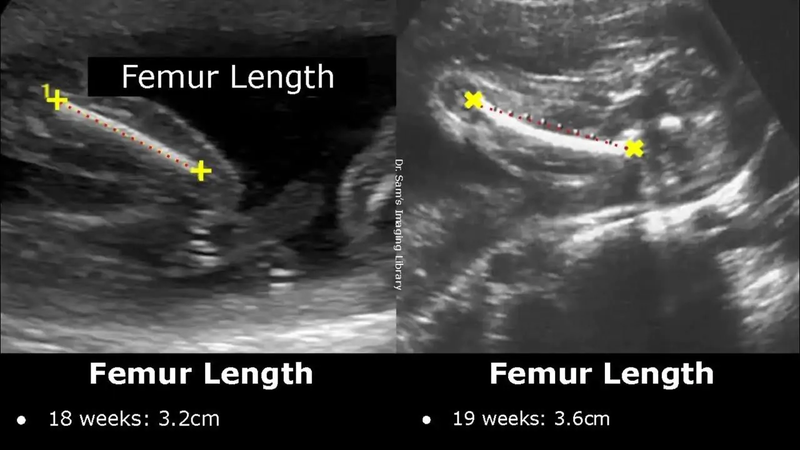

Siêu âm định kỳ giúp theo dõi sự phát triển của thai nhi và kiểm tra sự xuất hiện của bất kỳ vấn đề nào như dị tật bẩm sinh, vấn đề về dịch ối, hoặc vấn đề về dòng máu.